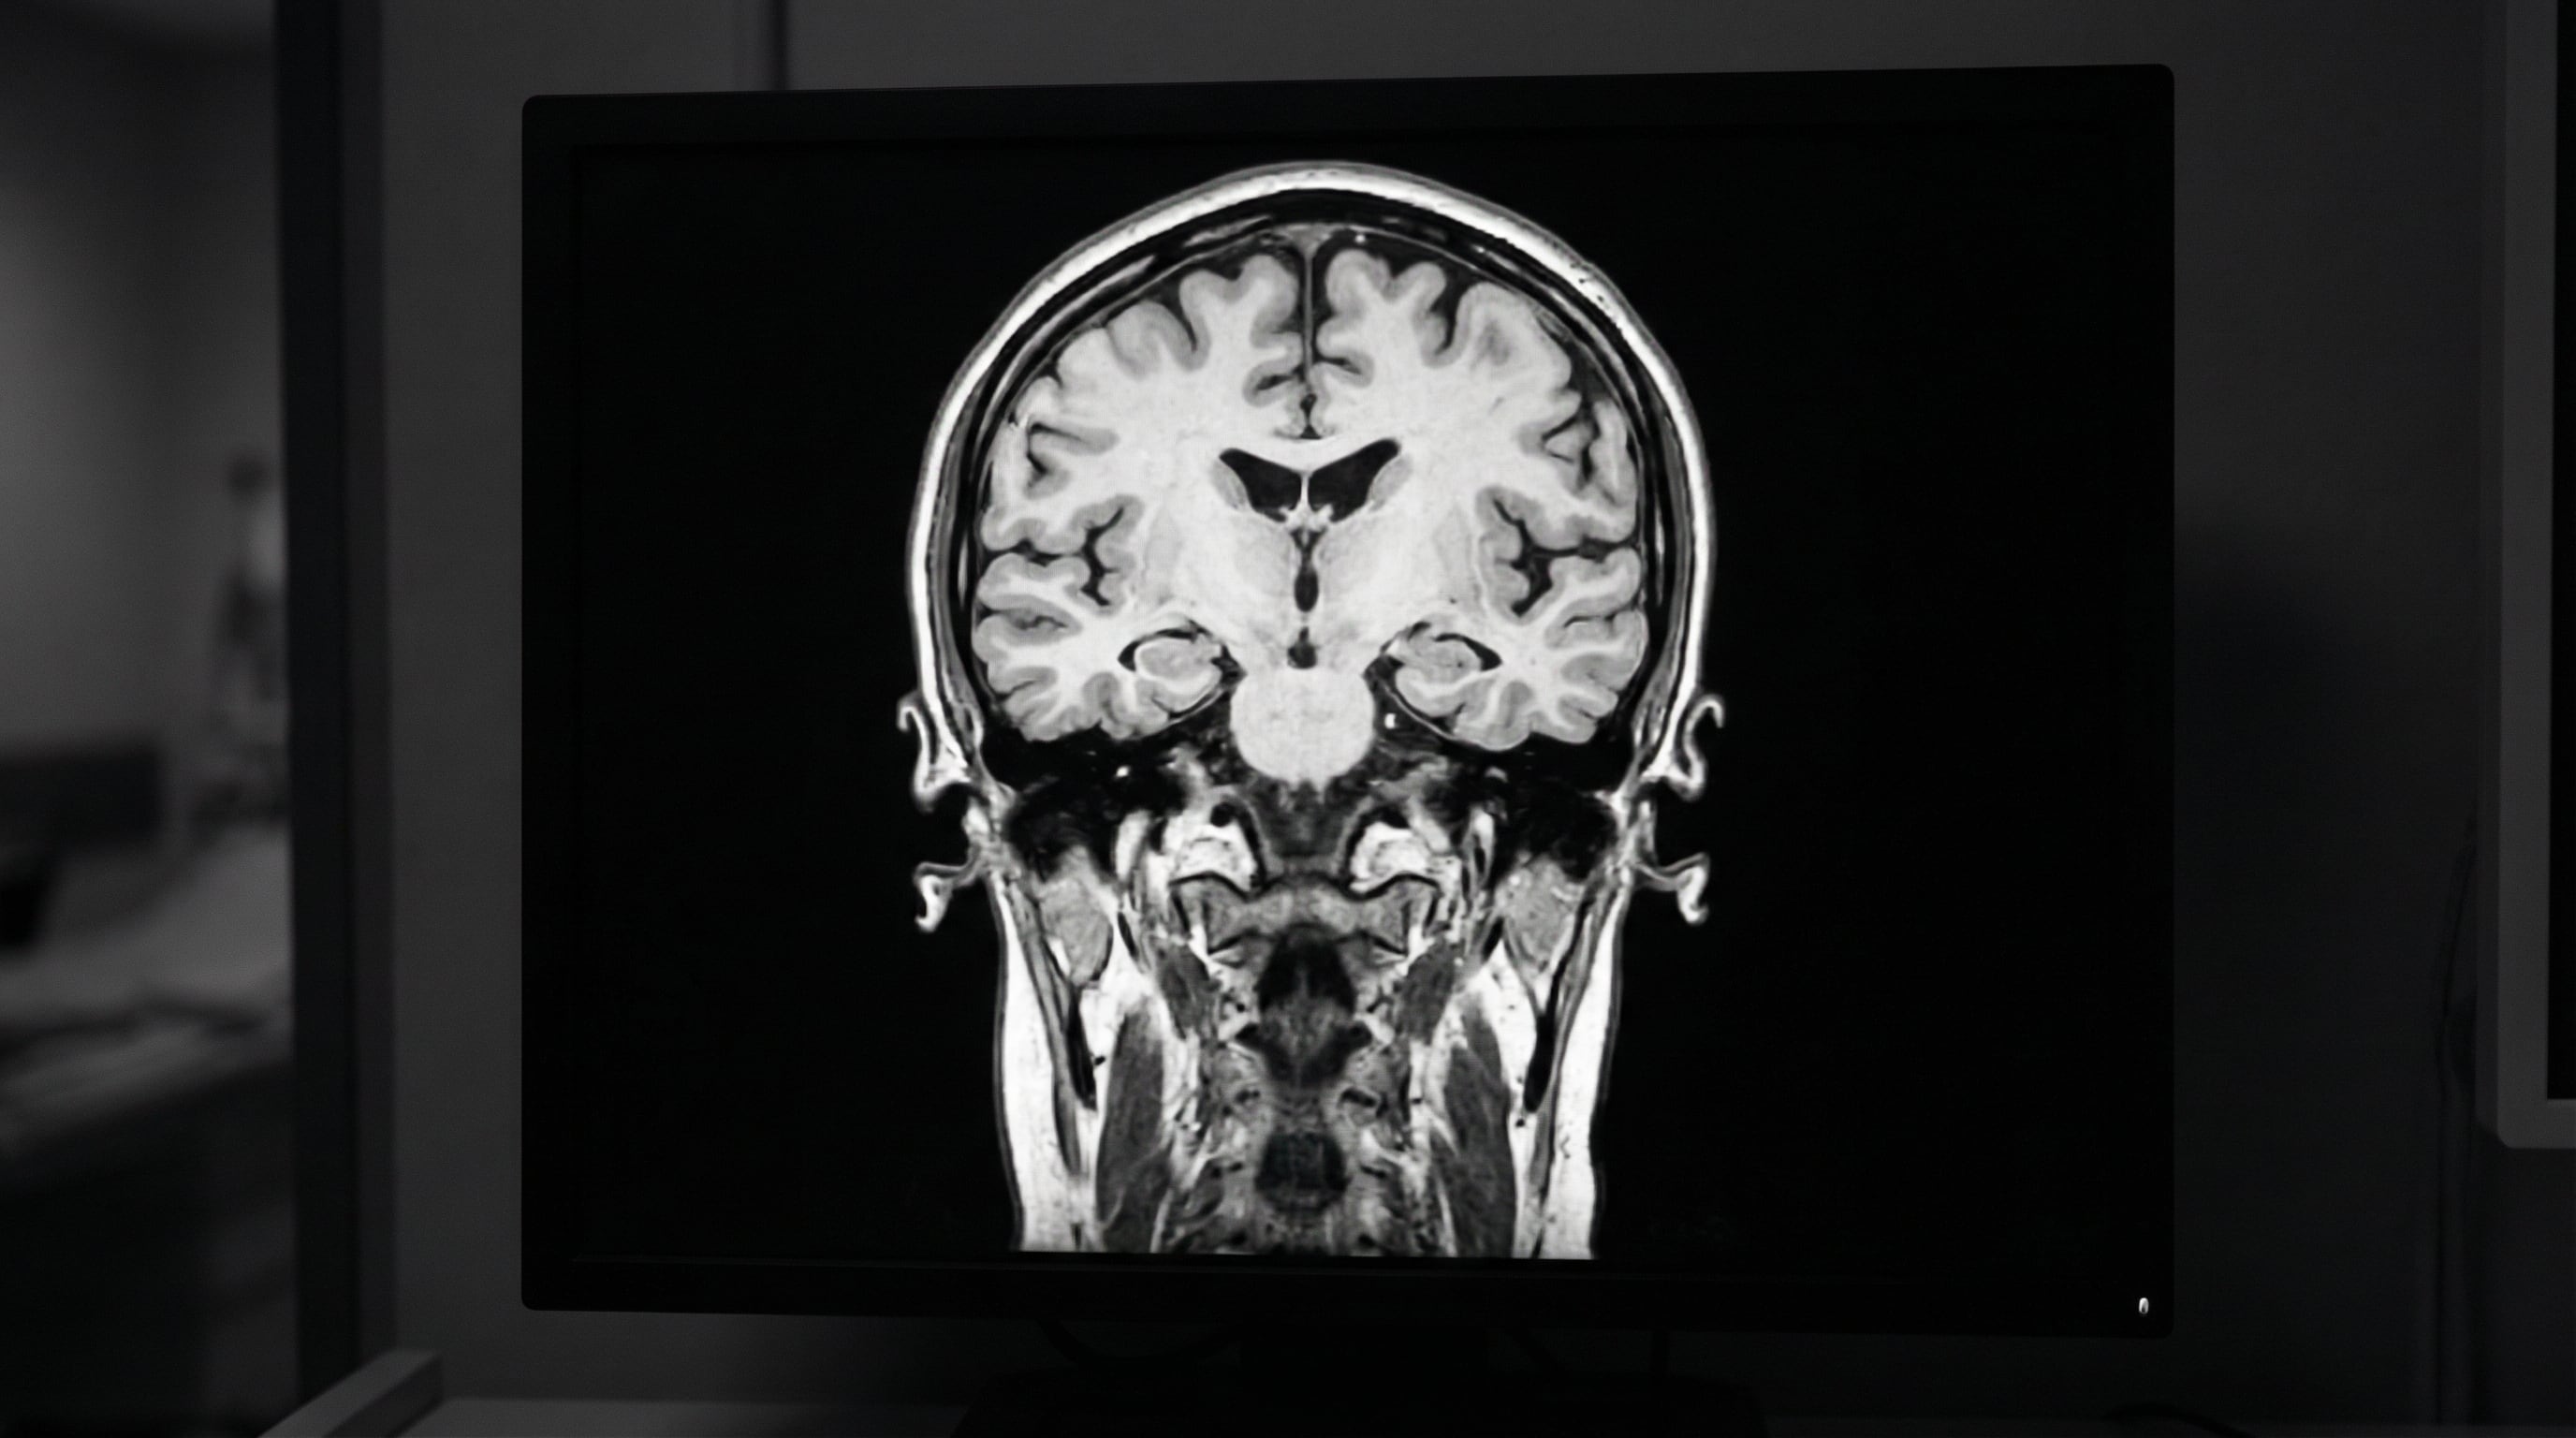

La memoria es un proceso complejo que permite al ser humano codificar, almacenar y recuperar información a lo largo del tiempo. Este fenómeno depende de la interacción entre varias áreas cerebrales, cada una con funciones específicas en la formación y el manejo de los recuerdos. El hipocampo resulta fundamental para la creación de memorias nuevas, mientras que la amígdala interviene en la vinculación de los recuerdos con las emociones. Por su parte, la corteza prefrontal se encarga de la memoria de trabajo y la toma de decisiones.

La comprensión detallada de cómo operan estas áreas y etapas ayuda a identificar qué factores pueden alterar la memoria. El envejecimiento, el estrés y ciertas enfermedades pueden afectar negativamente estas estructuras cerebrales y, en consecuencia, la capacidad para recordar, explica el Hospital Liv de Estambul.

Por otro lado, la pérdida progresiva se desarrolla paulatinamente y puede ser síntoma de enfermedades neurodegenerativas, como el Alzheimer, la demencia con cuerpos de Lewy y la enfermedad de Huntington. En estos casos, la memoria empeora a medida que la afectación cerebral avanza. También pueden influir trastornos vasculares, tumores cerebrales, esclerosis múltiple y ciertas condiciones psiquiátricas.